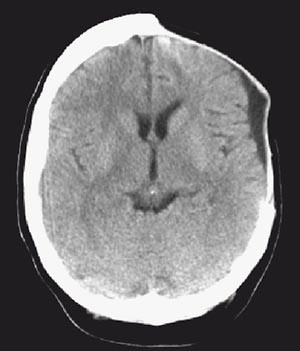

Det postoperative forløpet var ukomplisert. En uke postoperativt hadde pasienten ikke lenger afasi, og hemiparesen var gått betydelig tilbake. Tre uker postoperativt hadde hun normal nevrologisk status. Cerebral CT en måned postoperativt viste betydelig tilbakegang av ødem (fig 3). Fire måneder postoperativt ble beinlappen lagt tilbake, og cerebral CT viste minimale lavattenuerende forandringer frontalt på venstre side (fig 4).